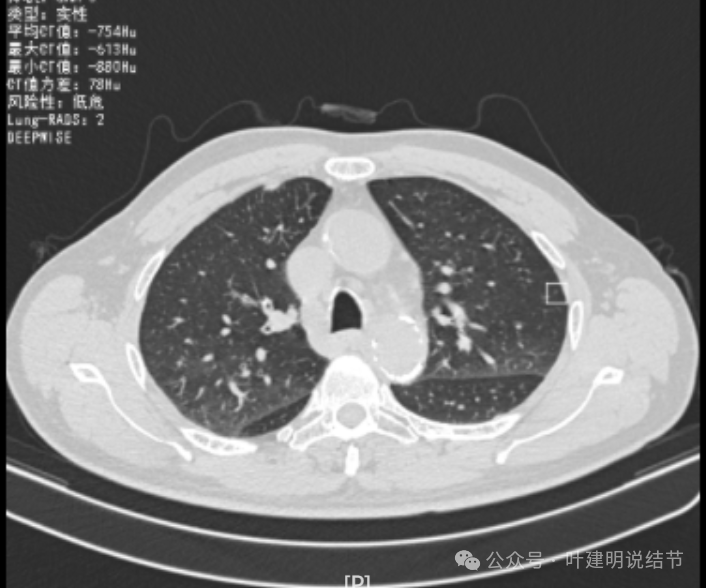

再看2024年6月时的影像:

右上没有明显变化,仍考虑良性可能性大。

左下也考虑良性,与2022年无明显变化。

右下新增病灶,混合密度,整体轮廓较清,瘤肺边界欠清。

有小血管进入,边缘毛糙。

局部有毛刺,但不够锐利;病灶感觉有一层晕似的,邻近胸膜下也有淡磨玻璃影。

实性密度为主,周围少许很淡的磨玻璃影。

边缘不平有毛刺,但不锐利;贴着胸膜但无明显牵拉。局部表面有浅分叶似的,但总体膨胀感不够。

病灶表面不光滑,边上有晕,邻近有淡磨,贴着胸膜无牵拉。

病灶边缘欠清晰,瘤肺边界稍模糊。较宽的基底贴着胸膜。

病灶有血管进入,有浅分叶,实性为主,邻近胸膜有片状淡磨玻璃影,近胸膜无牵拉。但有一定膨胀性。

病灶实性,与血管关系较为密切。

血管走向病灶,但似乎没有被病灶影响,有向内侧的分支甚至没有哪怕一点凹向病灶侧。整体显得偏模糊。

边缘区域杂乱,边糊。